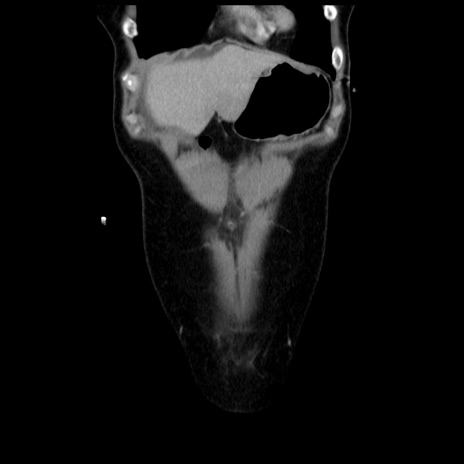

横断像

矢状断像